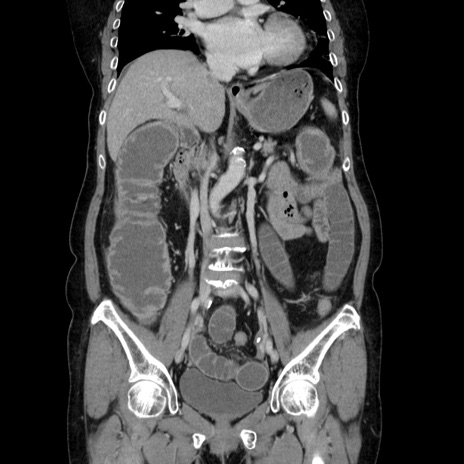

症例5(冠状断像)

【症例】70歳代女性

【主訴】お腹が張る

【現病歴】1週間くらい前から腹部膨満の自覚あり。昨日夜から増悪したため、本日救急外来受診。

【身体所見】意識清明、BT 36.5℃、BP 165/106mmHg、HR 80bpm、SpO2 98%、腹部:膨満、軟、自発痛・圧痛なし、触診にて不快感あり、腸蠕動音:減弱

【データ】WBC 12600、CRP 1.04